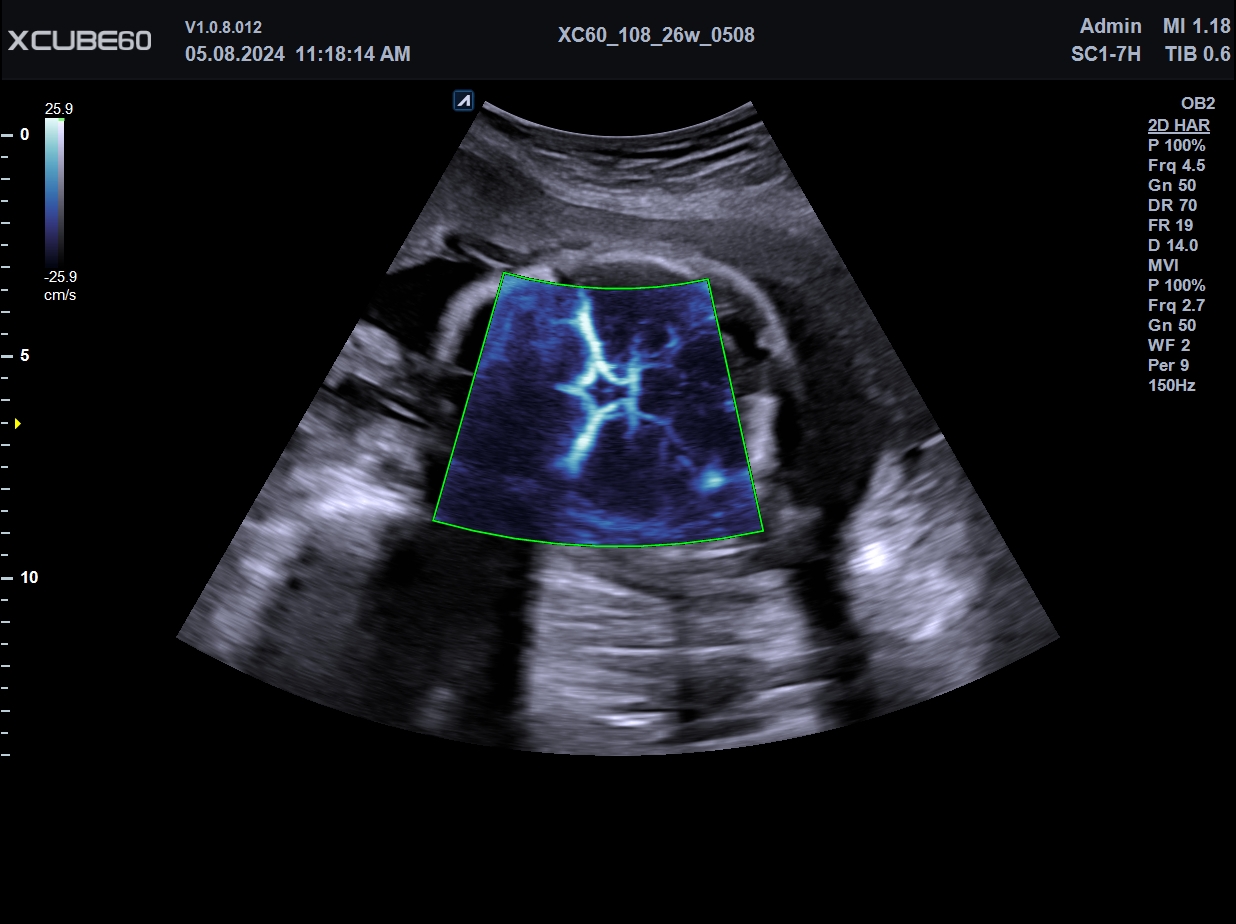

El X-CUBE 60 se desarrolló para brindar un entorno de trabajo cómodo a la usuaria. El rendimiento óptimo de imagen se logra gracias a la arquitectura X+, el motor de imágenes de alta resolución de la serie X-CUBE, para un diagnóstico fiable de diversas enfermedades. Repetir el diagnóstico a diario agota al personal médico. Diversas funciones de medición automática, que se adaptan al flujo de trabajo del usuario, reducen el tiempo de diagnóstico, y la pantalla táctil de mayor tamaño y el panel de control intuitivo reducen la fatiga. Además, su tamaño compacto y versátil permite un uso eficiente del espacio en la sala de escaneo.

| Arquitectura del Sistema: | Arquitectura X+, Power View, FleXcan, SensitiView, X+ Cristal Signature, X+ Fit, Optimal Imaging Suite |

| Software Disponibles OB/GIN: | 3D/4D convexo y endocavitario, Live HQ, Volume Advance, Auto Translucencia Nucal (NT), X+ Auto Biometry, X+ Follicle, Silhouette View |